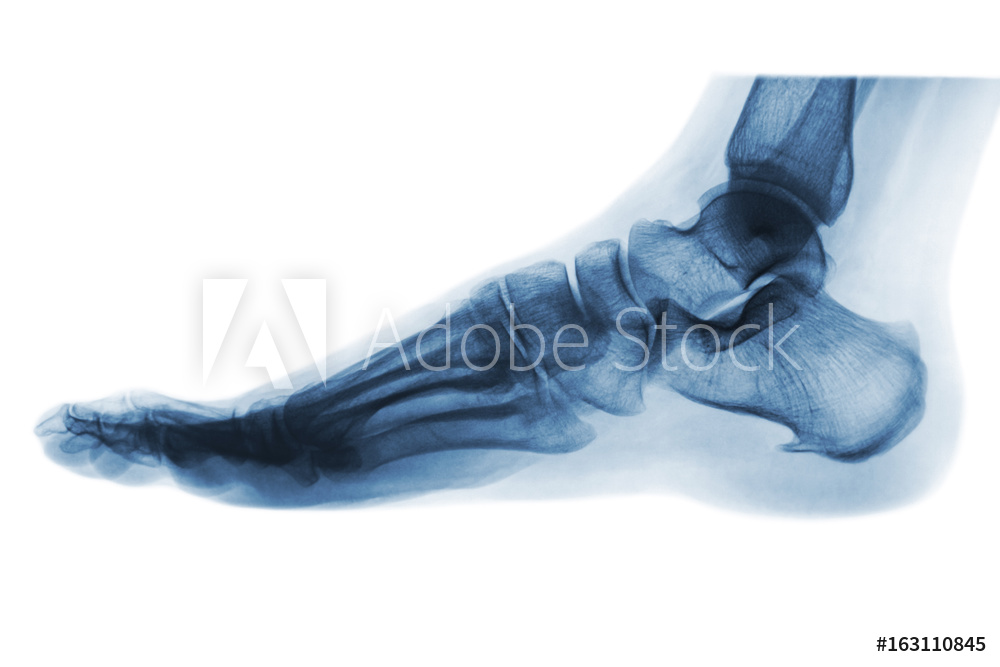

Das spezialisierte Team des Fußzentrums im St. Hildegardis Krankenhaus bietet Ihnen bei allen Erkrankungen, Fehlstellungen und Verletzungen von Fuß und Sprunggelenk individuelle und moderne Therapiekonzepte. Mit 26 Knochen, 32 Gelenken und einer Vielzahl von Bändern und Sehnen gehören Fuß und Sprunggelenk zu den komplexen Strukturen unseres Körpers – entsprechend entscheidend ist die Erfahrung des Ärzteteams für den Behandlungserfolg.